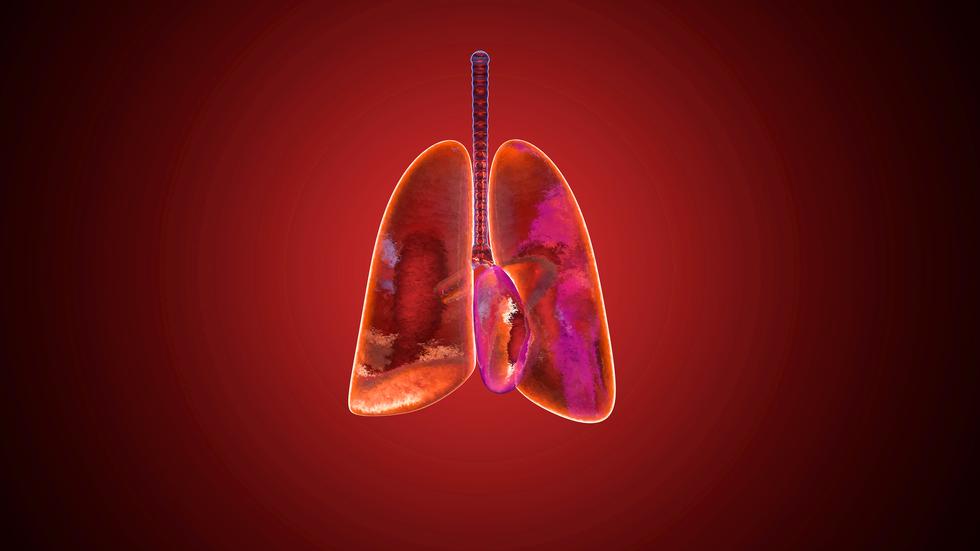

Lungenkrebs Neue Therapieformen machen Hoffnung

Aber nicht alle Erkrankte müssen alle Wegstrecken gehen – viele können heutzutage „unterwegs” geheilt werden oder haben zumindest eine lange erkrankungsfreie und behandlungsfreie Zeit vor sich. Wie man am besten mit der Diagnose Lungenkrebs umgehen kann und worauf man achten sollte erklärt Katja Schiffke (Psychoonkologin) im Video.. Bleibt ein Lungenkrebs unbehandelt, leben Patienten in der Regel höchstens zwei Jahre. Die Behandlung kann heilend sein und der Patient bis ins hohe Alter leben. Manchmal schlägt die Therapie aber nicht an, und der Krebs führt in wenigen Monaten zum Tod. Dazwischen ist alles möglich.